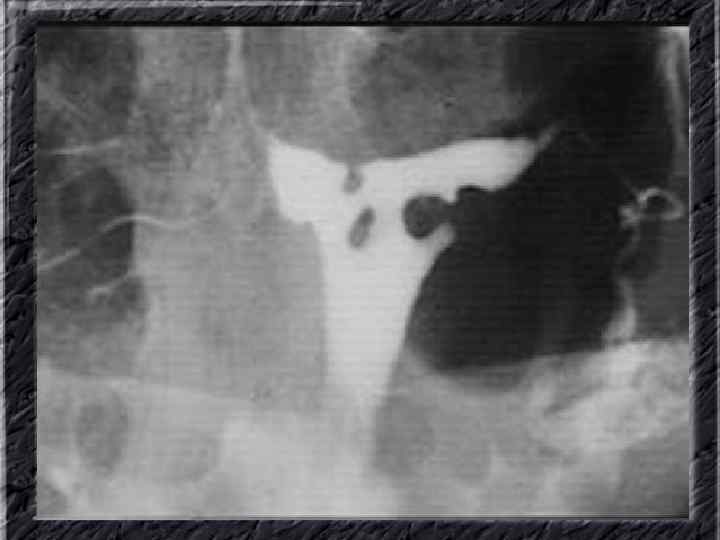

Названия слайдов: • • • Слайд 51. Ультрасонография: интерстициальный и истмический отделы маточной трубы. Слайд 52. Лапароскопия: неизмененная правая маточная труба. Слайд 53. Ультрасонография: многокамерная форма сальпингита. Слайд 54. Лапароскопия: относительно равномерное утолщение маточной трубы при гидросальпинксе. Слайд 55. Лапароскопия: вид маточной трубы при гидросальпинксе. Слайд 56. Гистеросальпингография: неравномерное расширение и деформация маточных труб. Слайд 57. Прервавшаяся трубная беременность: плод; макропрепарат. Слайд 58. Гематосальпингс, развившийся вследствие внутреннего разрыва плодо-вместилища при трубной беременности; макропрепарат. Слайд 59. Лапароскопия: значительное увеличение участка маточной трубы при трубной беременности. Слайд 60. Лапароскопия: скопление крови в полости малого таза в результате трубного аборта.